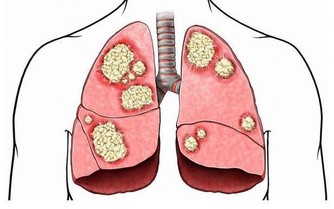

首先明確腎有哪些功能?

第一,腎是負責生成尿液的器官;

第二,人體在新陳代謝的過程中,腎是負責排泄代謝物和有毒物;

第三,維持人體內水喝電解質的平衡;

第四,維持人體的酸鹼平衡;

第五,腎還負責調節內分泌功能。